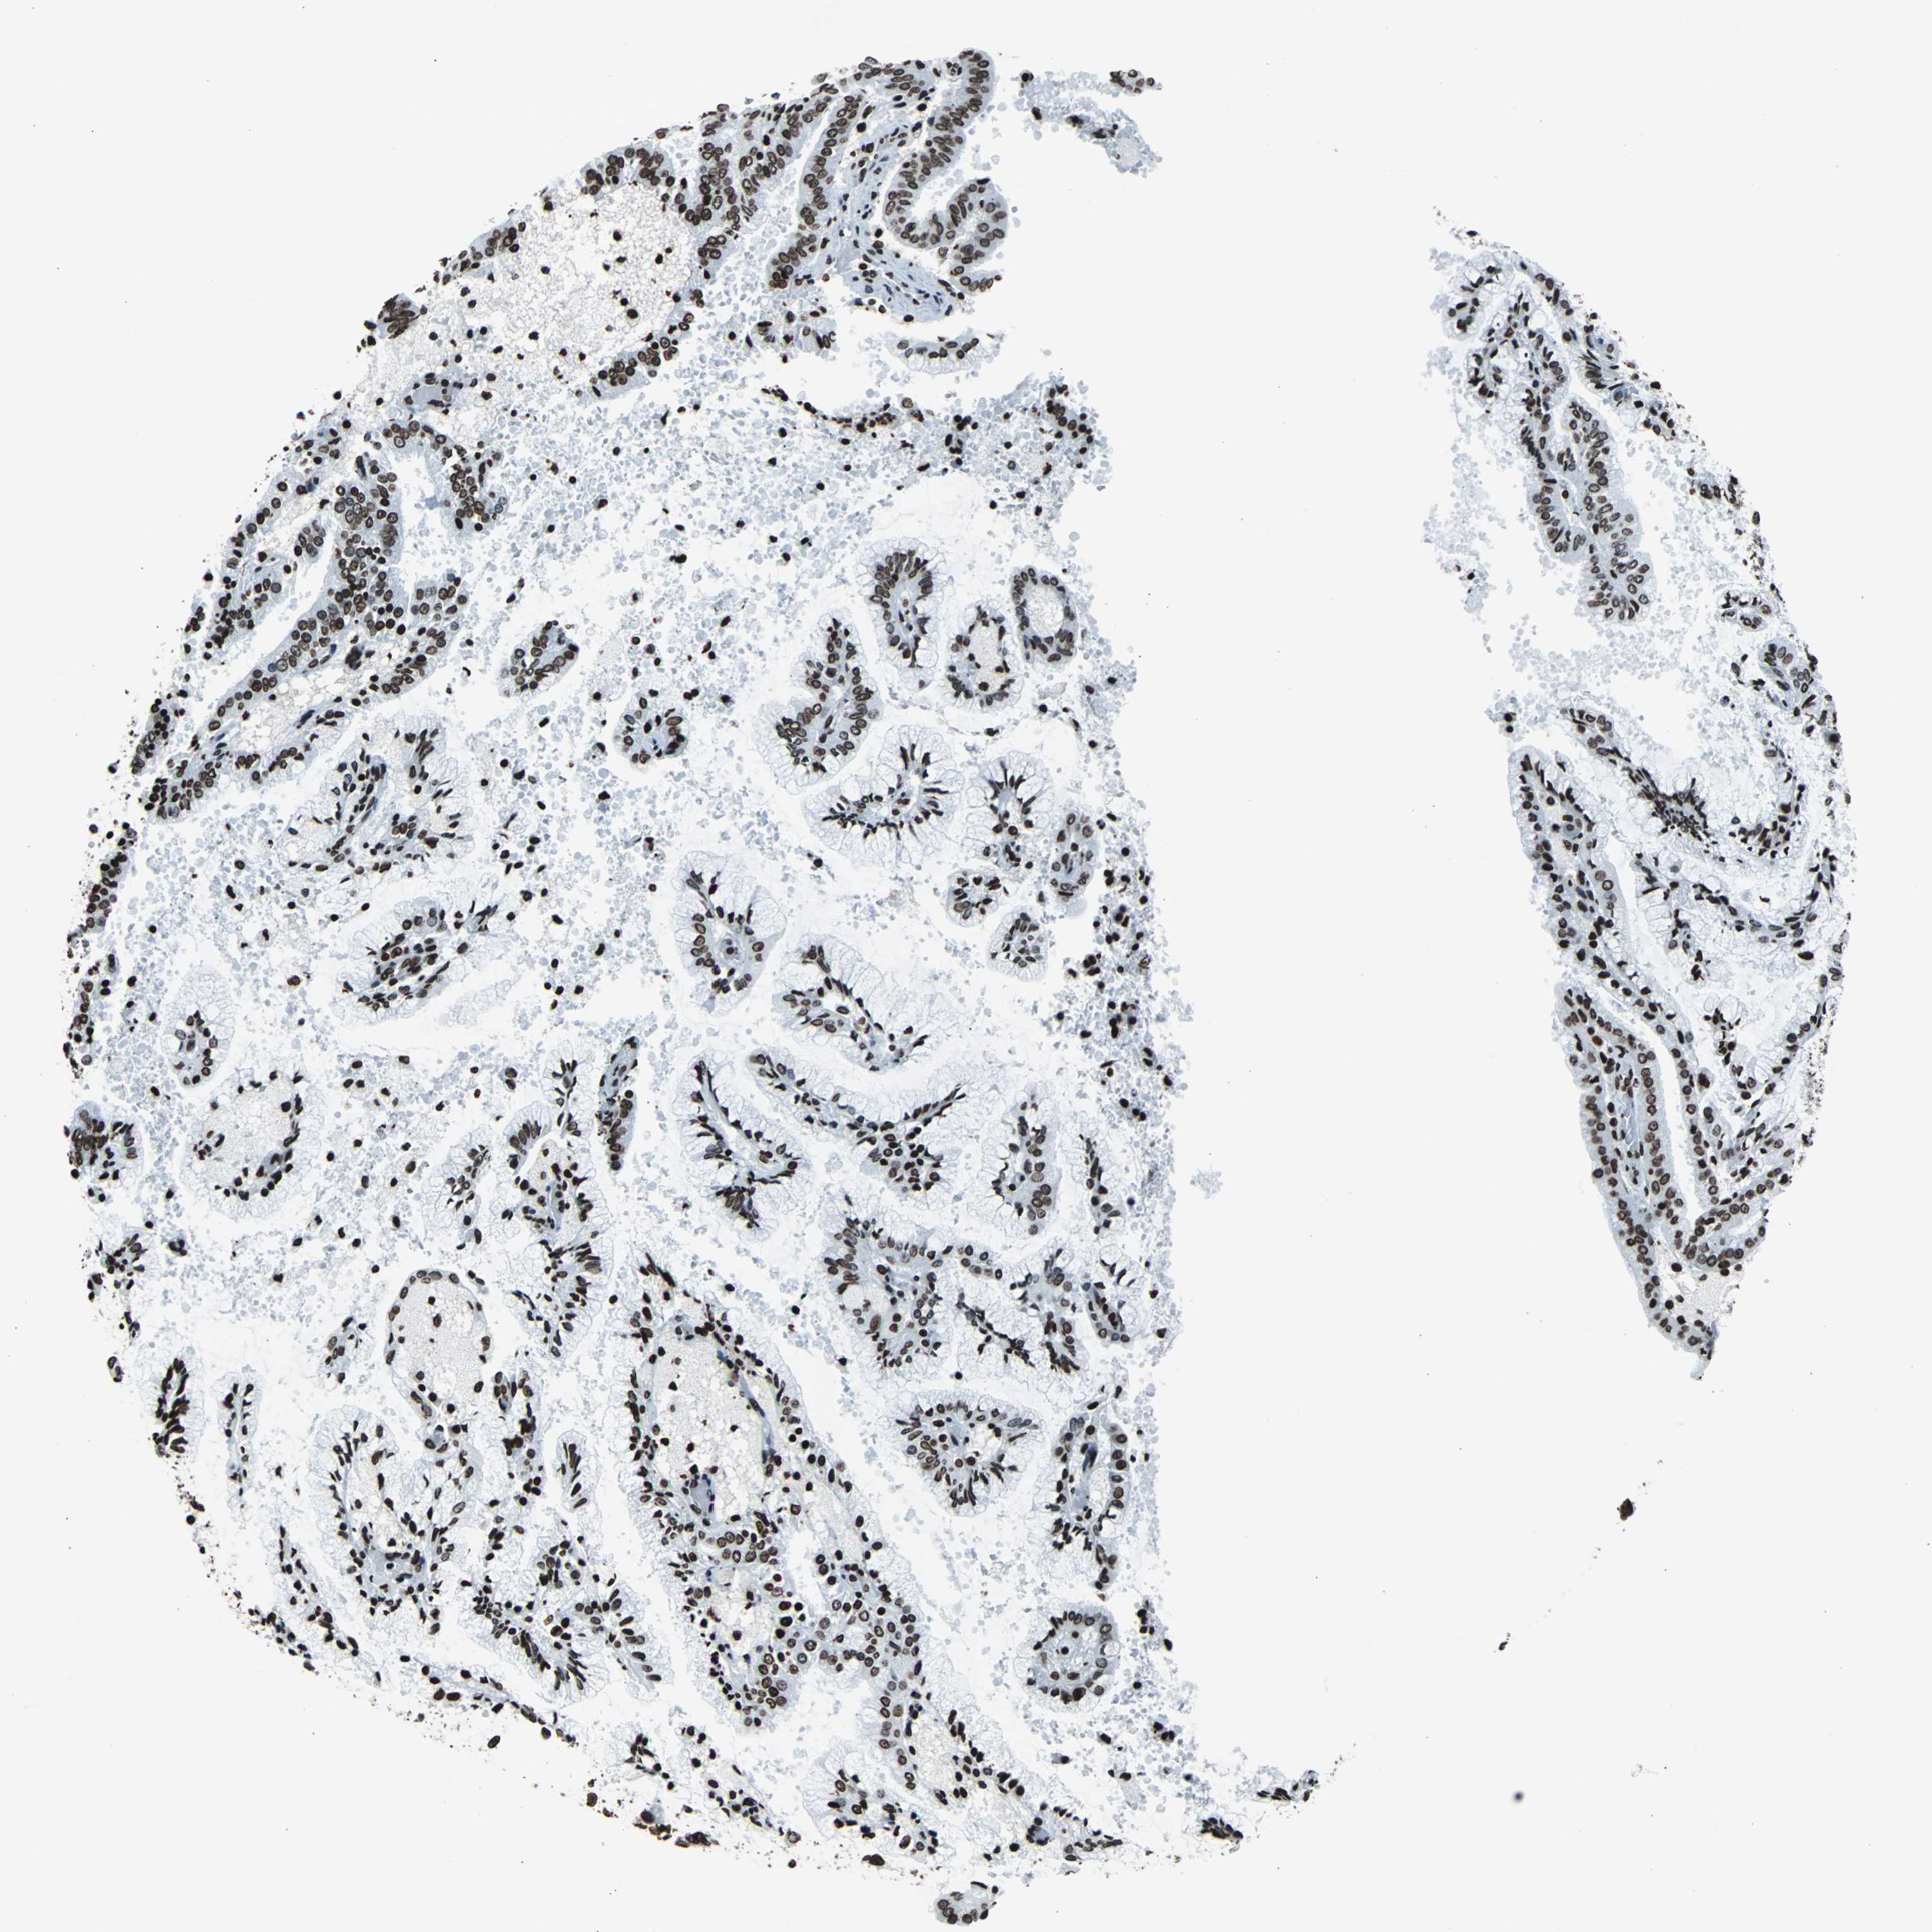

ENDOMETRIAL CANCER - Protein expressioni

A mouse-over function shows sample information and annotation data. Click on an image to view it in a full screen mode. Samples can be filtered based on level of antibody staining by selecting one or several of the following categories: high, medium, low and not detected. The assay and annotation is described here.

Note that samples used for immunohistochemistry by the Human Protein Atlas do not correspond to samples in the TCGA dataset.

Antibody stainingi

Antibody staining in the annotated cell types in the current human tissue is reported as not detected, low, medium, or high, based on conventional immunohistochemistry profiling in selected tissues. This score is based on the combination of the staining intensity and fraction of stained cells.

Each image is clickable and will lead to virtual microscopy that enables deeper exploration of all samples and also displays staining intensity scores, fraction scores and subcellular localization as well as patient and tissue information for each sample.

Antibody HPA042205

Antibody HPA043013

Antibody HPA048671

Antibody CAB007814

Staining

High

Medium

Low

Not detected

Intensity

Strong

Moderate

Weak

Negative

Quantity

>75%

75%-25%

<25%

None

Location

Nuclear

Cytoplasmic/membranous

Cytoplasmic/membranous,nuclear

Adenocarcinoma, NOS